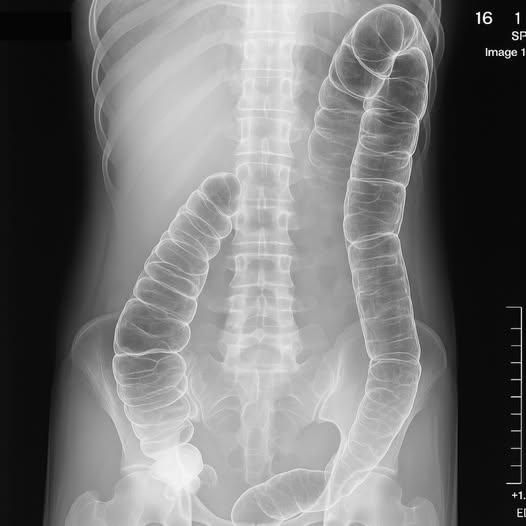

Lo que muestra esta radiografía

La radiografía revela un intestino grueso dilatado, lleno de materia fecal acumulada. El colon, que debería estar evacuando los desechos a diario, estaba prácticamente bloqueado. Esta acumulación presiona los órganos internos, provoca malestar general, inflamación, dolor y, en casos graves, puede causar intoxicación intestinal.

El cuerpo estaba literalmente reteniendo sus propias toxinas.